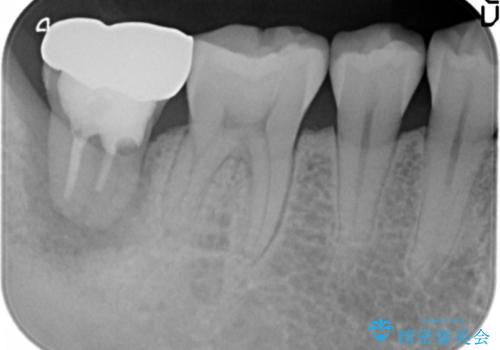

- 奥歯の歯ぐきからウミが出ている、抜歯が必要と他院で言われたとのことでした。

抜歯を行い、インプラントを入れていきました。

炎症で骨が少なかった場所には骨補填材を置いています。